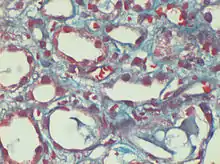

Dilated peri-tubular capillaries filled with sickled RBCs, original Gomori's trichrome stain, × 400.[1]

Gömöri trichrome stain is a histological stain used on muscle tissue.[2][3]